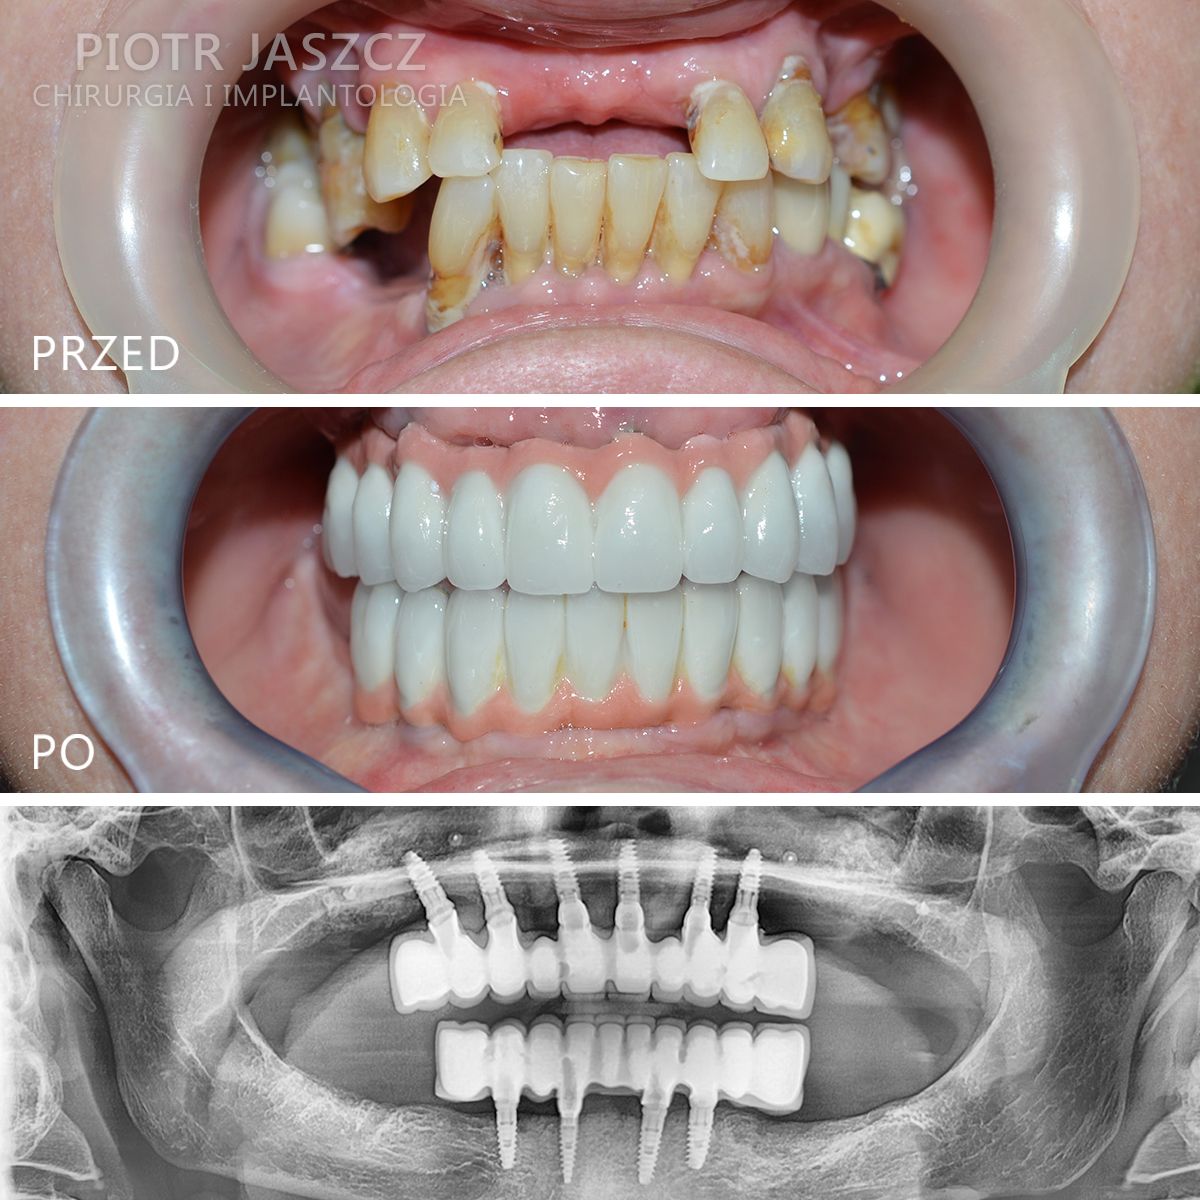

Wykonuje zabiegi odtworzenia zębów w 24h, polegające na usunięciu wszystkich zębów w szczęce lub żuchwie, wszczepieniu implantów metodą All-on-4 lub All-on-6 oraz oddaniu mostów na wszczepionych implantach w 24h. Metamorfozy szczęki w 24h.

Wszczepił ponad 4000 implantów.